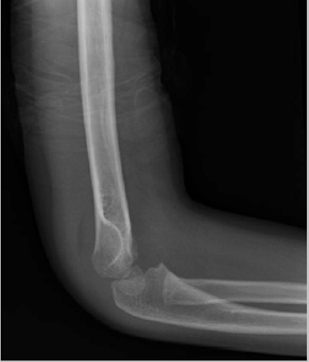

Hình 1: Gãy trên lồi cầu xương cánh tay Gartland độ I với bất thường vỏ xương và dấu hiệu bờm mỡ ở phía sau (Courtesy of Stephanie A. Russo, MD)